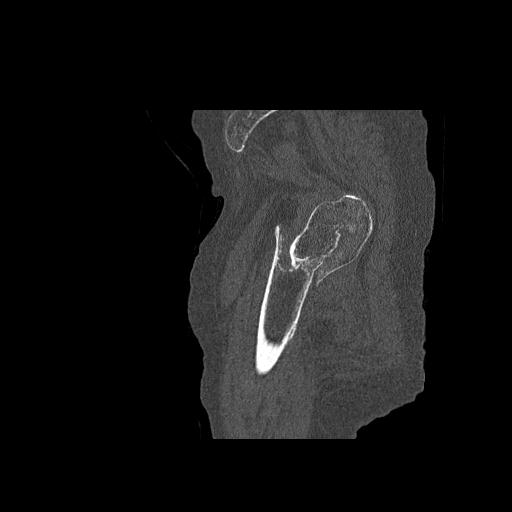

110286 2/17 股関節 2R 74歳女性 右人工骨頭

82084 1/14 1/20 股関節 2R 78歳男性 右人工骨頭

91569 3/25 両股正面とラウエン 70歳女性 人工骨頭+バンクーバー